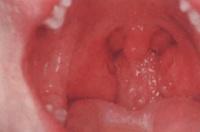

全身症状不明显。局部症状主要是咽痛咽干不适,咽部痒感,口臭等。扁桃体一

慢性扁桃体炎图解

般都比较大。扁桃体隐窝内的细菌素被吸收,而引起身体的变态反应,常有消化不良头痛、疲乏无力、低热等症状。检查时见扁桃体充血,特别咽腭弓充血。有时呈暗红色,扁桃体表面有瘢痕,凹凸不平,有的有小脓点,挤压扁桃体可挤豆渣样分泌物,有时颌下淋巴结肿大。